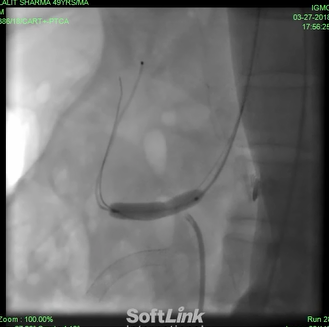

Management: Once symptoms of mesenteric ischemia are there, revascularization is required. Open surgical repair was standard care of treatment in CMI, but at present initial approach is endovascular repair( Figures 3-5) in around 80% of patients[12]. It is minimally invasive, has high initial success rate and has few complications13. However, plain balloon angioplasty has lower success rate and high rate of restenosis, stent is almost always implanted[13,14]. Restenosis can still occur in around 40% patients and 20% may require repeat intervention[15,16]. Also, the results of angioplasty may depend upon the vessel revascularized. In a study, primary patency was better in SMA group than in coeliac artery group17.

Figure 3: Tight stenosis of SMA, in a patient of CMI, missed for 8 years, in many hospitals. Upper and lower GI endoscopy, ultrasound of abdomen, coronary angiography were normal. Weight loss of 14 Kg in last two months.

Figure 4: Implantation of stent in same patient of CMI.

Figure 5: Wide open SMA after stenting. All symptoms disappeared. Weight gain of 4 kg in two weeks.